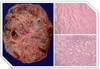

Tipo mais comum de CA de ovário?

Cistoadenocarcinoma seroso.

(linhagem epitelial)

Grupos histológicos? (3)

ECG:

- Epitelial/adenocarcinoma (90%);